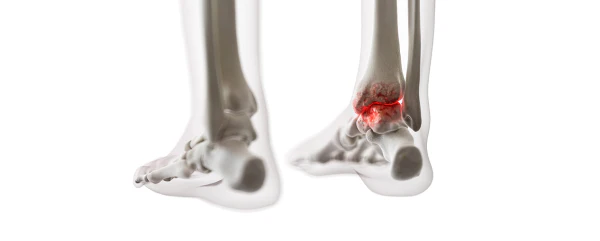

통풍을 적절히 치료하지 않을 경우, 발작성 관절염의 빈도가 증가하고 침범하는 관절 수도 더 많아지며, 회복에 필요한 시간도 증가합니다. 반복적인 관절염은 관절을 점차 손상시키며, 만성적인 관절염으로 진행될 수 있습니다. 또한 통풍성 결절이라 불리는 덩어리가 관절 주위나 피부 조직에 나타날 수 있습니다. 이러한 결절은 요산 결정체의 덩어리로 어느 부분에서든 형성될 수 있으며, 주로 팔꿈치, 귀, 손가락, 발가락, 발목 등에서 발생할 수 있습니다. 때로는 요로 결석을 형성하기도 합니다.

4) 엄지발가락 관절에 염증이 잘 발생하는 것이 특징이며, 무릎, 발, 발목, 손목, 팔꿈치 등 다른 관절에서도 발생할 수 있습니다.